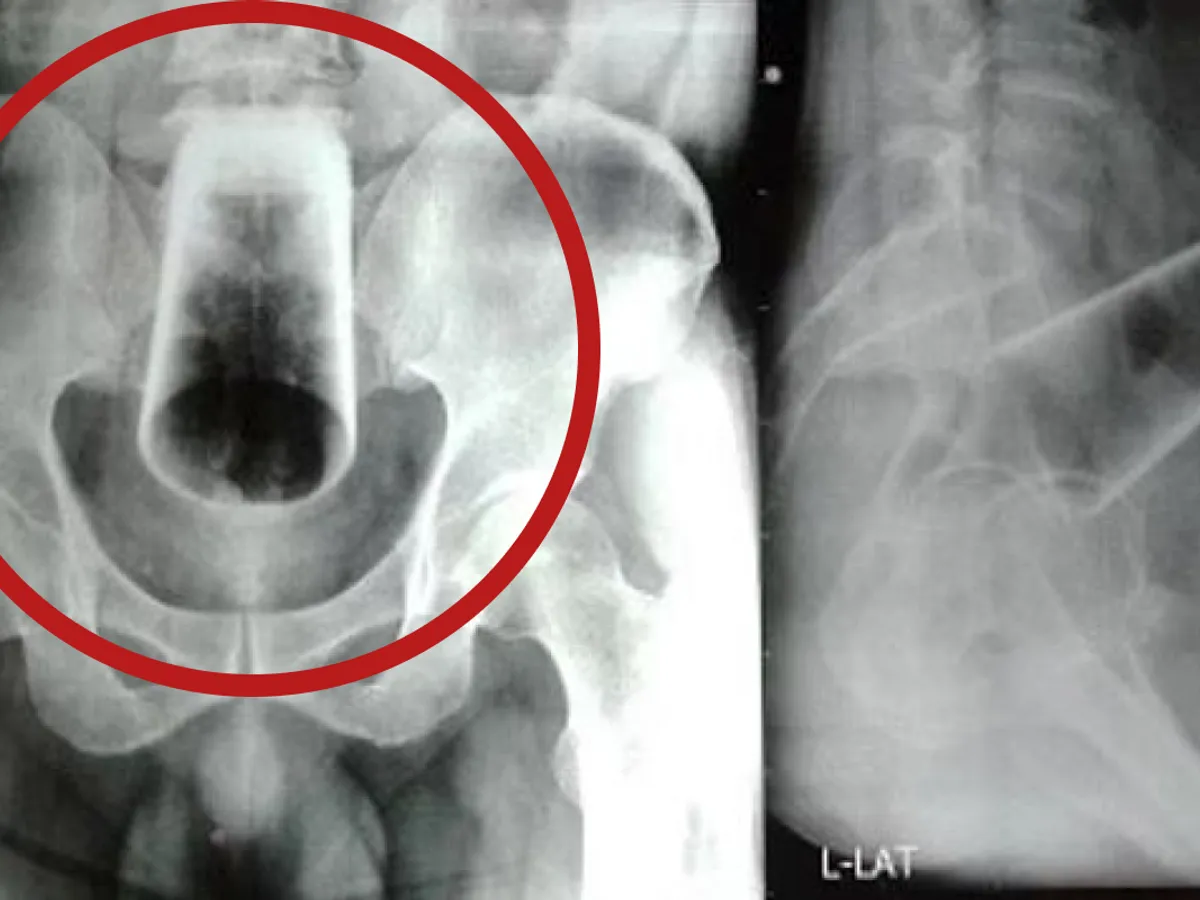

A încercat să scoată singur paharul, dar încercările sale au eșuat la fel ca și cele ale medicilor care, după ce i-au făcut o radiografie tipului, nu au reușit să prindă paharul care se deplasase în abdomenul său.

Foto: Nepal Medical Association